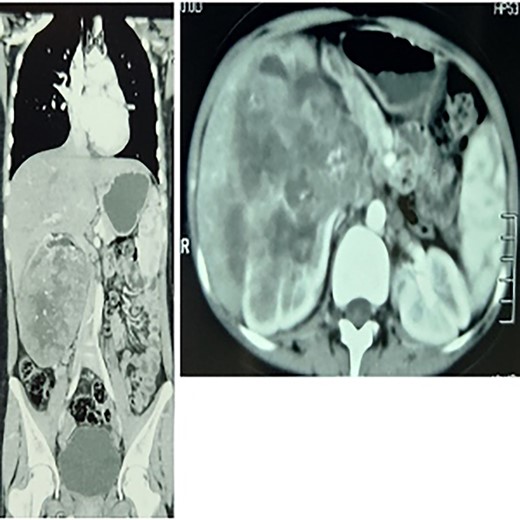

On imaging, the abdominal ultrasound revealed a huge heterogeneous mass of size 13 × 14 cm encompassing the right kidney. MSCT with contrast of the chest, abdomen and pelvis showed a large right centrally necrotized tumor, homogenously enhancing the contrast material. No distant thoracic metastases, periaortic, inferior vena cava or visceral lymph nodes enlargement, no ovarian mass. There were many stones that filled the left kidney (Fig. 1).

To the left: coronal section multiple-slice computed tomography slice showing the lump at the greatest diameter, to the right a transverse section showing a renal mass.